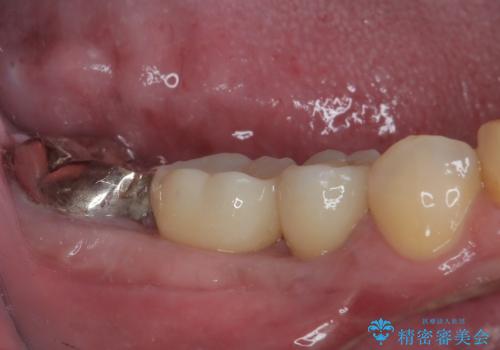

- むし歯を放置したことで、歯茎で膿が腫れ上がったしまったとのことで来院された患者様です。

ブリッジの支台歯が痛みを覚え、近医でブリッジを切断してもらって以降、そのままにしてしまったとのことでした。

問題が起きていた手前の歯から膿が出てきたことを自覚して当院を来院されましたが、既に歯根破折をしており、抜歯が必要な状態でした。

咬合力が非常に強い患者様であり、2歯欠損のブリッジ(しかも大臼歯は失活歯)は歯根破折のリスクが高すぎると判断し、抜歯部および欠損部に対して、インプラントによる補綴治療を行うこととしました。